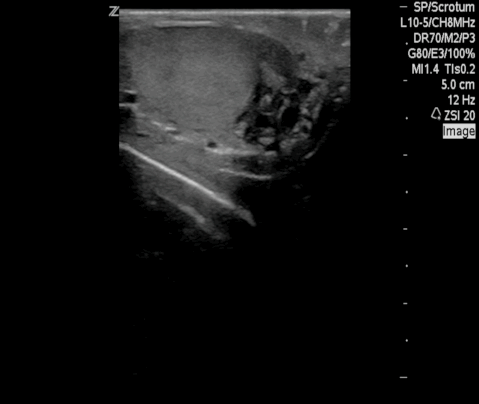

Filarial Dance Radiology Case Radiopaedia Org

Filarial Dance Sign On Scrotal Ultrasound W Bancrofti This Grepmed

Scrotal Filariasis The Importance Of Filarial Dance Sign In Scrotal Ultrasound

Scrotal Ultrasound Shows The Characteristic Filarial Grepmed